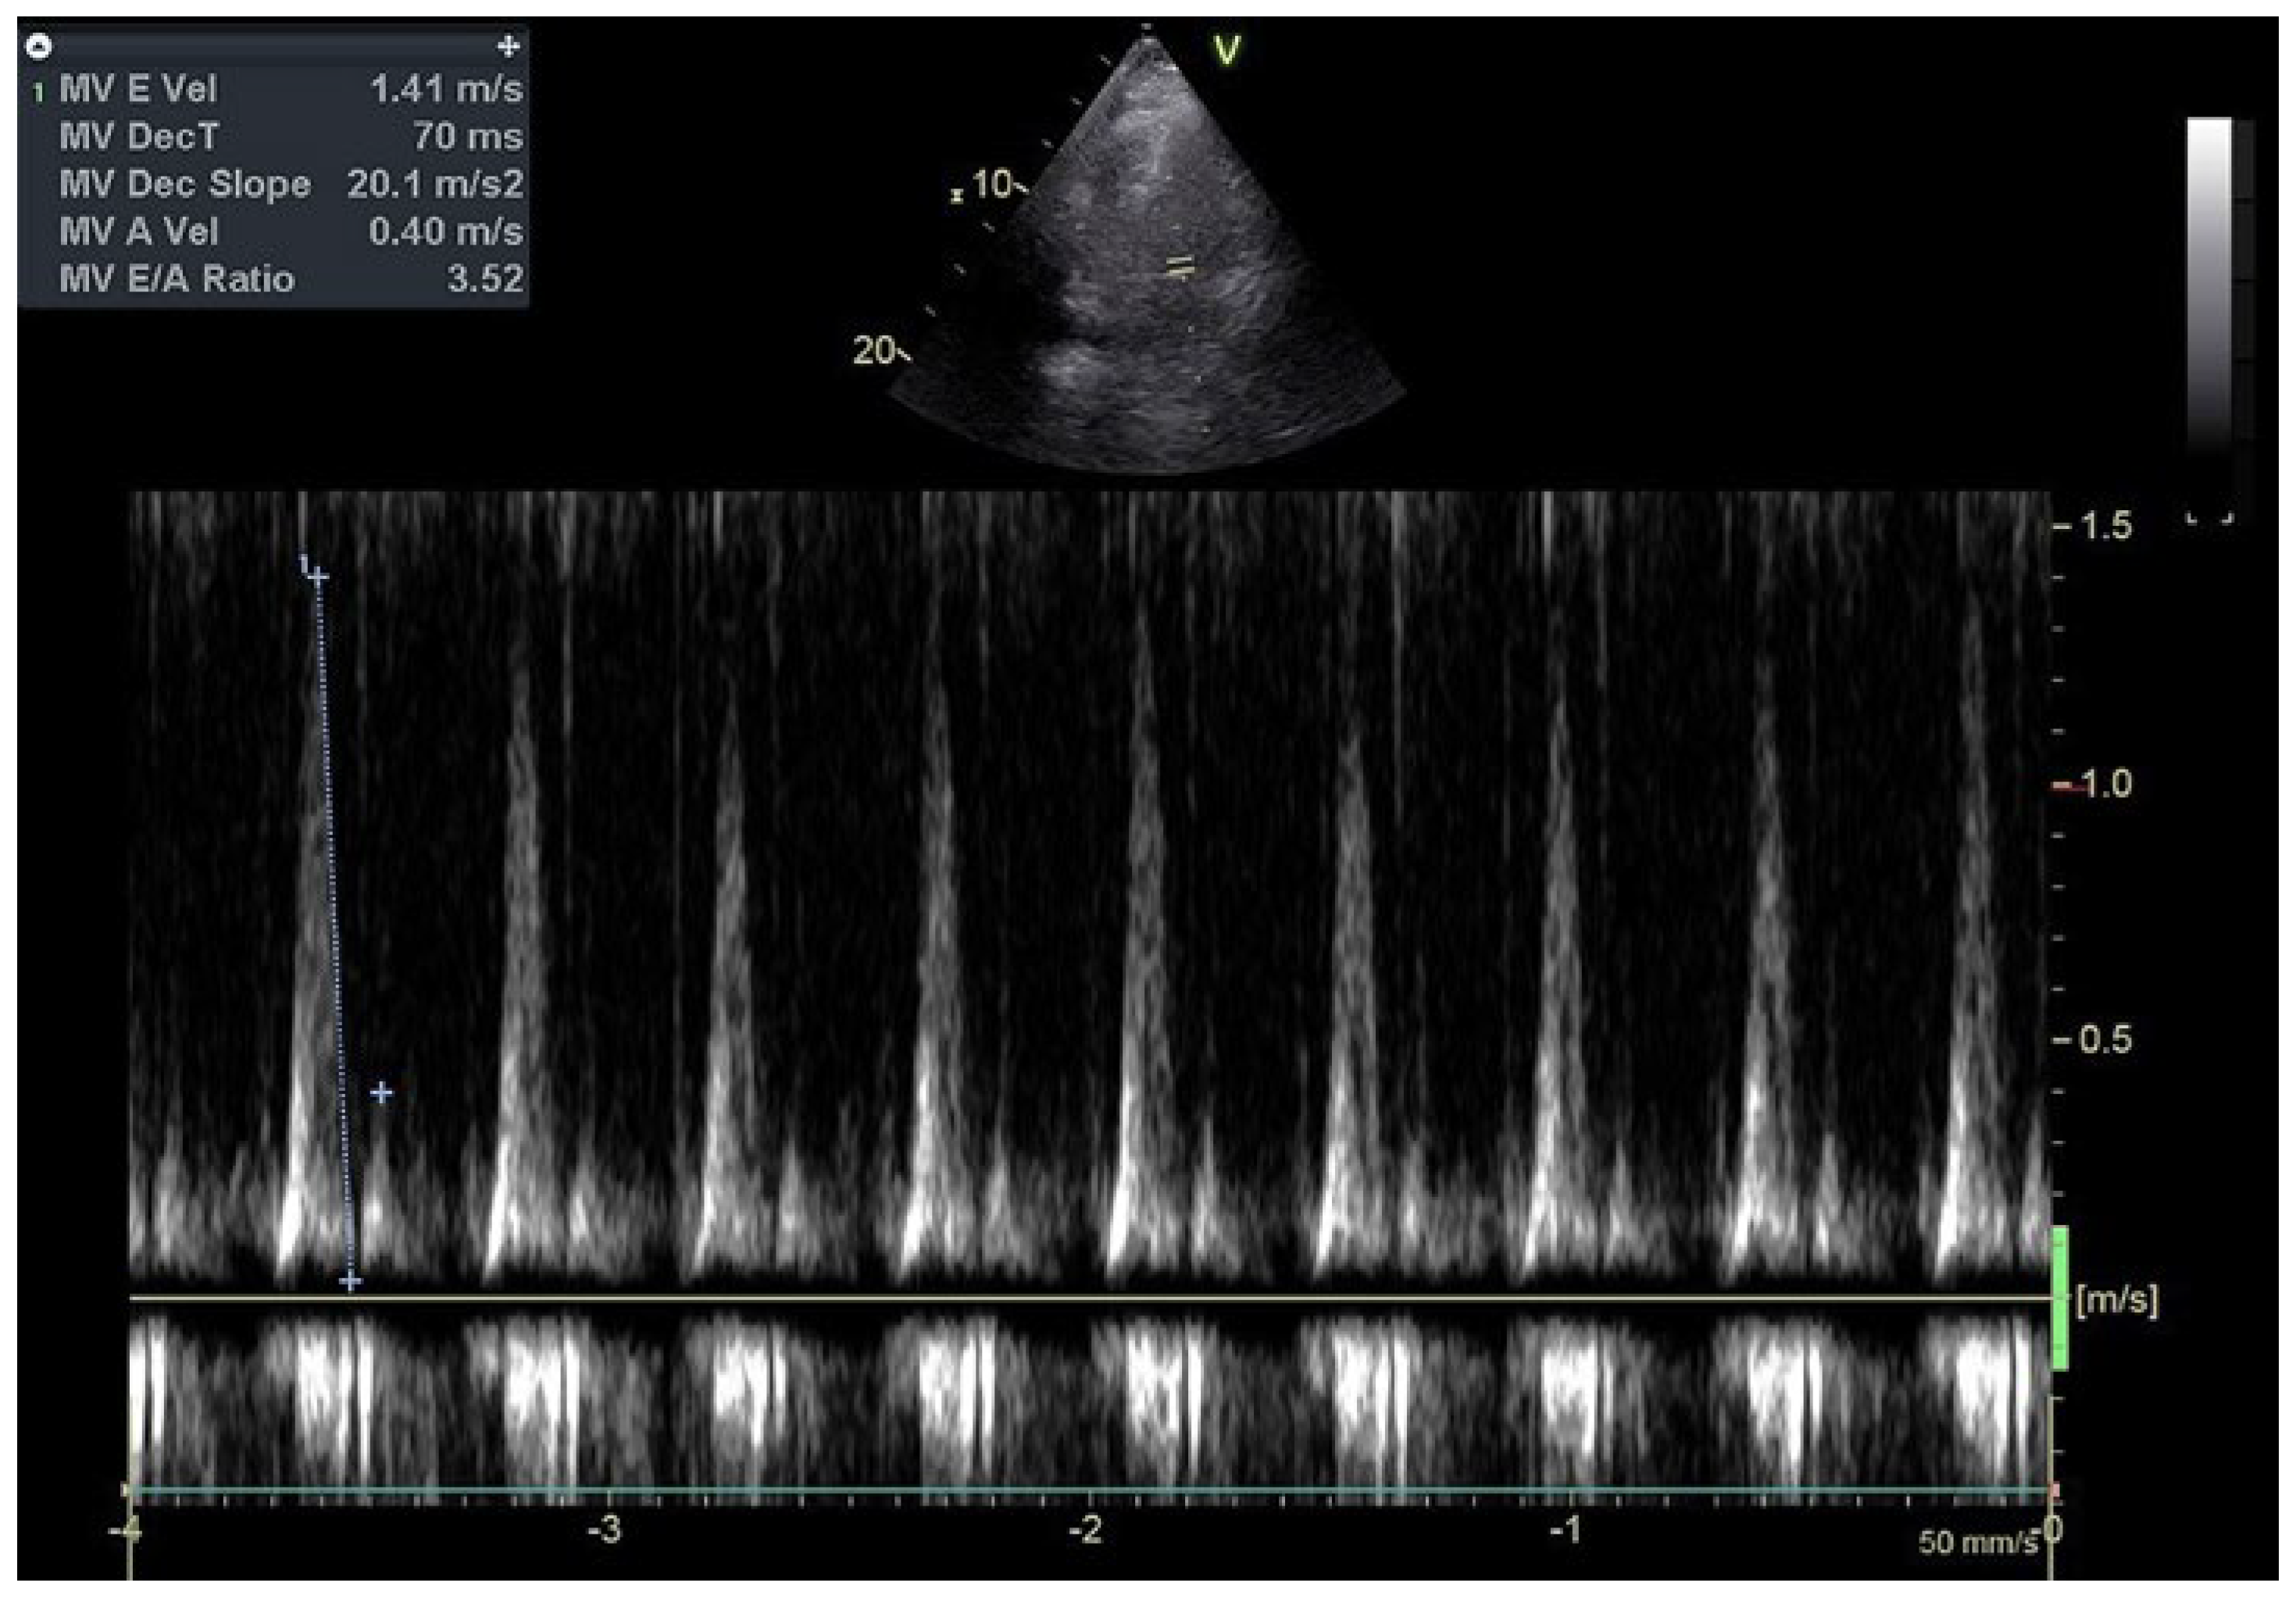

Relapsing Terlipressin-Induced Acute Pulmonary Oedema in a Patient with Hepatorenal Syndrome

Case description